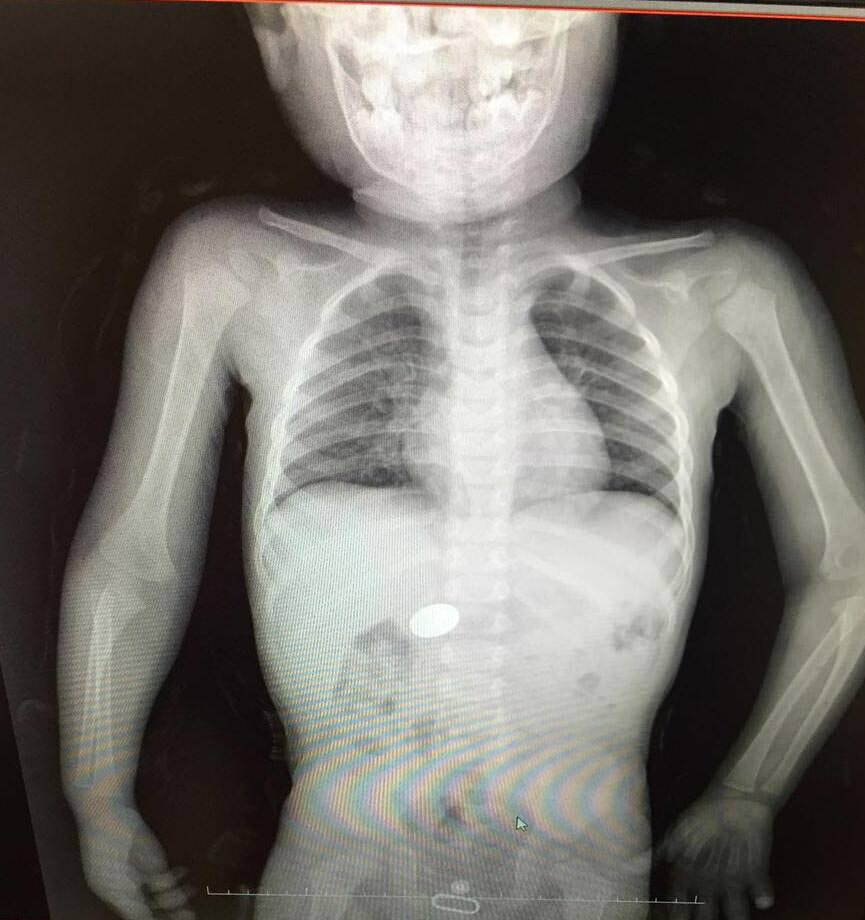

Bu objelerden en tehlikelisinin piller olduğuna dikkat çeken Doç.Dr. Maşallah Baran, "Piller kimyasal mekanizmayla mukozayı yakıyor, özellikle yemek borusu çok duyarlı pillere, hele ki yeni takılmış bir pilse saatler içinde şahit olduğum bir kaç vaka var, yemek borusunu kömür haline getirebiliyor" dedi.

"Çocukların nefes ve borusu ile midelerinden çıkartılan, anahtarlık, madeni para, saat pili, ataç, çengelli iğne ve çivi gibi objeler görenleri şaşkına çevirdi. "